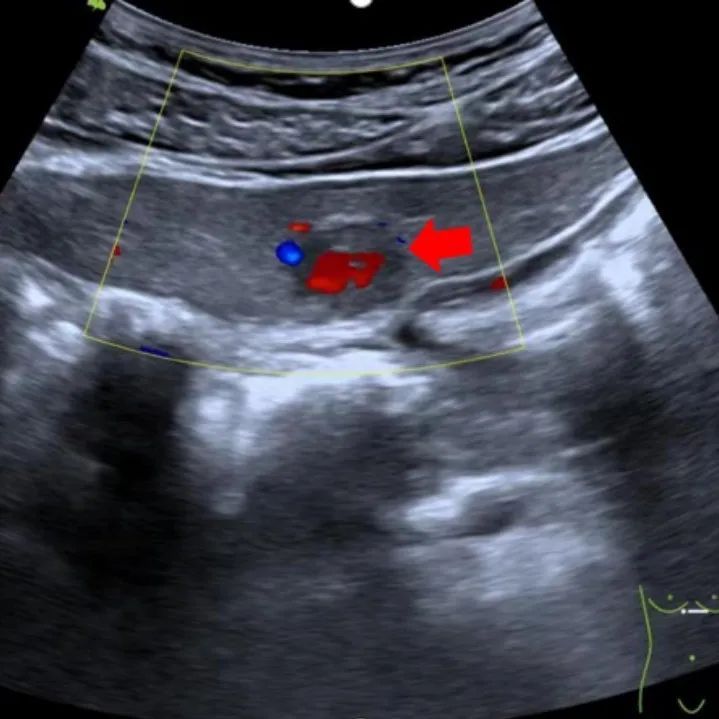

病灶可探测到一支血流由病灶外部进入病灶内(即滋养动脉)

在超声造影下,FNH动脉相快速离心性高增强,约40%的病灶内可见滋养血管由中央向周围呈轮辐状放射。

(就像横过来切的桔子一样)